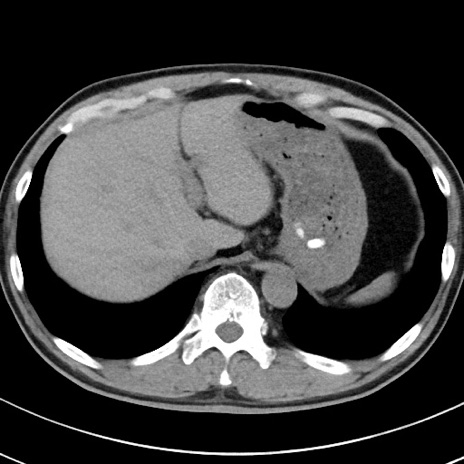

【腹部TIPS】症例29 参考症例 CT(横断像)

症例

70歳代男性